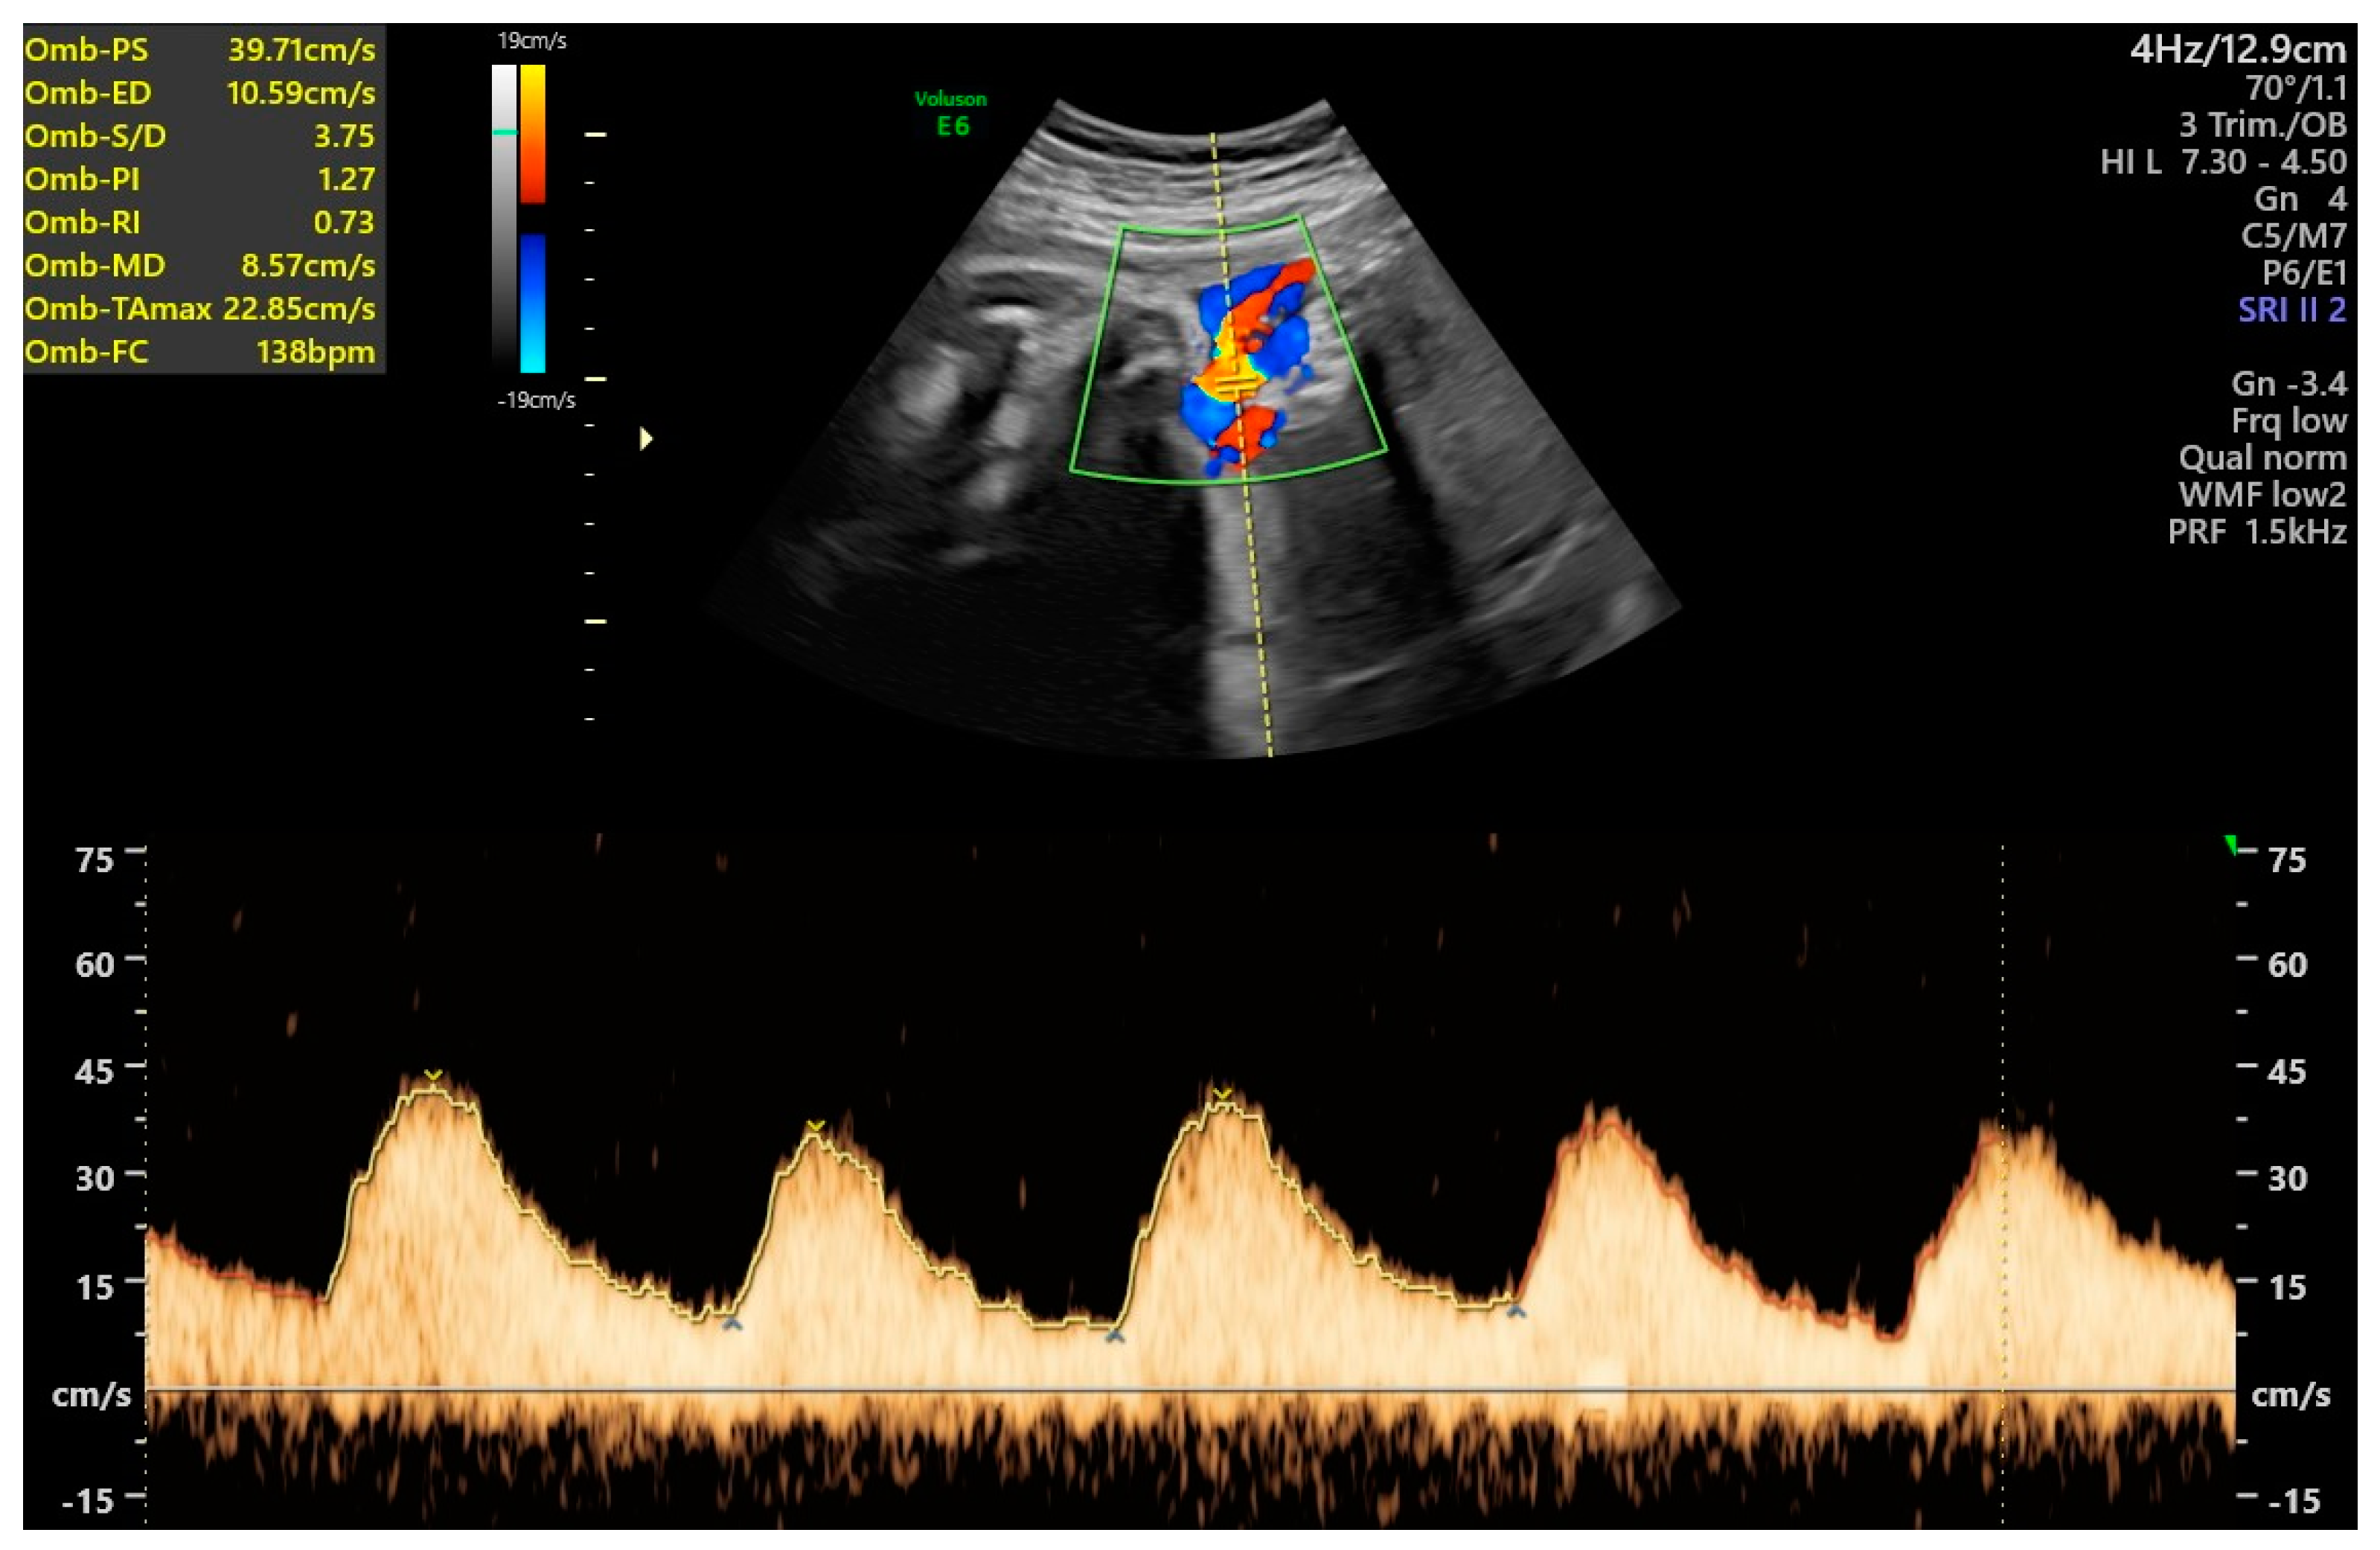

- Ferraguti, G.; Merlino, L.; Battagliese, G.; Piccioni, M.G.; Barbaro, G.; Carito, V.; Messina, M.P.; Scalese, B.; Coriale, G.; Fiore, M.; et al. Fetus morphology changes by second-trimester ultrasound in pregnant women drinking alcohol. Addict. Biol. 2020, 25, e12724. [Google Scholar] [CrossRef]